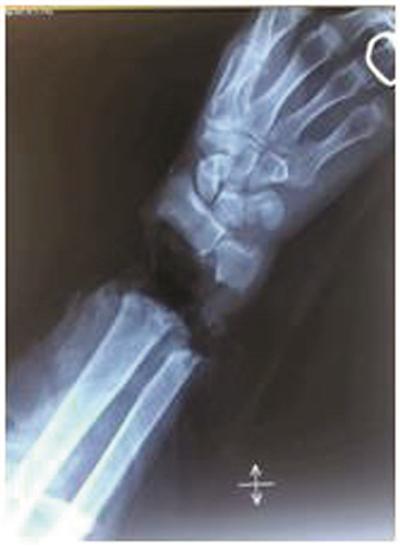

手腕骨断裂图片

手腕骨断裂图片,手骨断裂的照片

2017年最后一例手腕骨(月骨经舟骨)脱位,手法整复成功,完美收官.

21岁大学生掰手腕,"吧嗒"一声悲剧了!